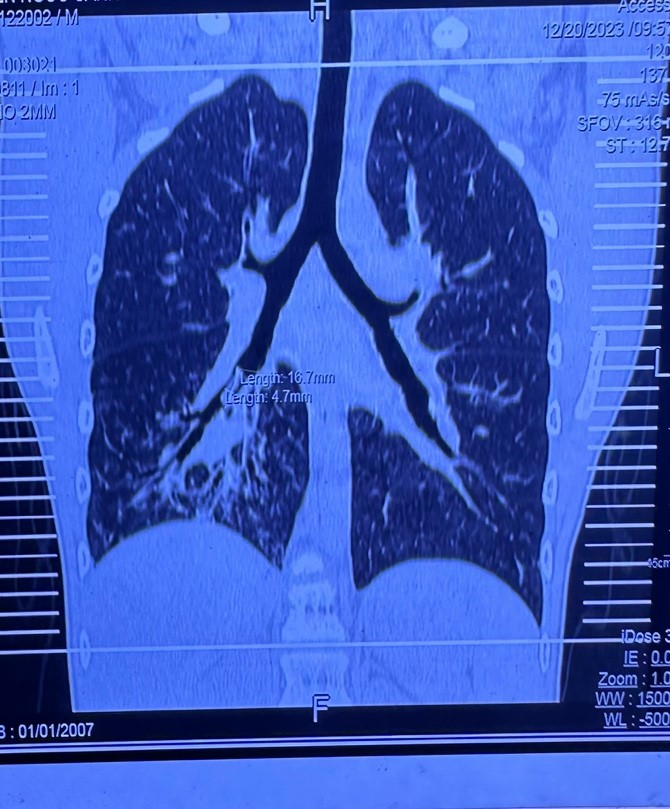

Tại Bệnh viện Phạm Ngọc Thạch bé được điều trị phác đồ lao phổi, tái khám mỗi 10 ngày /1 lần, đợt tái khám thứ 3 tình trạng vẫn không cải thiện, bé ho nhiều, XQ phổi không giảm, CT Scan phổi nghi là dị vật nên cho thuốc về uống, tái khám sau 10 ngày.

Sau đó tái khám thì không còn thấy dị vật, xét nghiệm lao âm tính, chẩn đoán viêm phổi phải. Bé về quê khám tại Bệnh viện chuyên lao và bệnh phổi Bình Định, tại đây chụp CT Scan phổi lại nghi dị vật đường thở nên người nhà xin chuyển Bệnh viện Nhi Đồng 1 nội soi đường thở.

Sáng 25/12, ekip phẫu thuật của khoa Tai Mũi Họng Bệnh viện Nhi Đồng 1 đã sẵn sàng cho ca dị vật khó và hy hữu này, vì đây là 1 trường hợp dị vật nằm trong phổi quá lâu và rất sâu ở phế quản hạ phân thùy phổi bên phải.